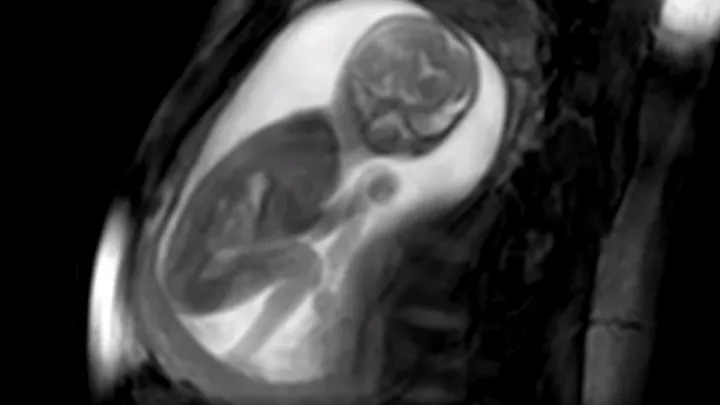

Door een extreem gedetailleerd 3D-model van het hart van een baby die nog in de buik zat, werd een hartafwijking zo duidelijk zichtbaar dat artsen het leven van het kind konden redden. Daarover schrijft de . Toen de Londense Kirbi-Lea Pettitt 20 weken zwanger was, ontdekten artsen twee gaten in het hart en een vernauwing van de aorta van het ongeboren kind. Het leven van de baby stond op het spel. Pettitt besloot mee te doen aan de studie van de onderzoekers om zo nog een kans te hebben om het leven te redden van haar kind. De wetenschappers legden MRI-foto's die uit verschillende hoeken waren genomen over elkaar heen. Met een nieuw computerprogramma konden ze een gedetailleerde 3D-weergave van het hart maken. Zo konden ze de hartafwijking exact bestuderen en een behandelplan maken. Direct na de geboorte onderging de baby met succes een hartoperatie. Violet-Vienna is nu elf maanden en kerngezond. In de toekomst kunnen veel hartproblemen bij baby's zo worden verholpen, denken de onderzoekers.